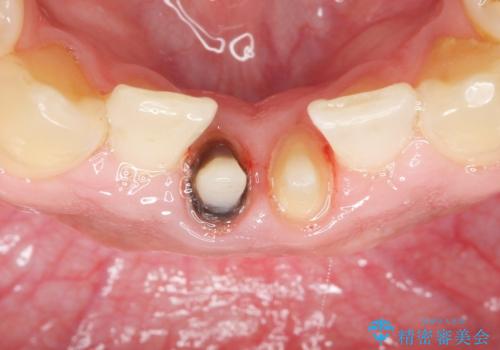

- 下の前歯の色が気になることを主訴に来院された患者様です。

下の前歯は金属の土台により黒くなり、隣の歯も神経が死んで暗く変色していました。

神経が死んでいる歯の根管治療を行った後、セラミッククラウンによる補綴治療を行いました。